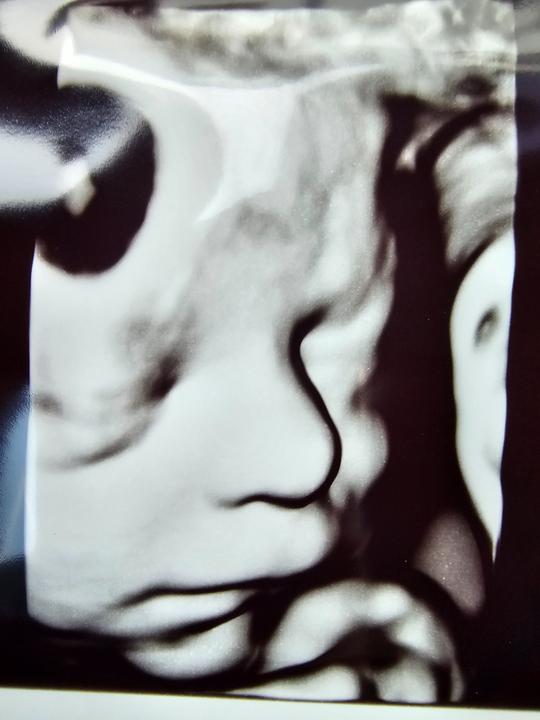

Dnes má nás Bruno mesiac🥰 Boli sme na kontrole u lekárky a dostali veľkú pochvalu, všetko dobehol, motoricky popredu,klbiky ukážkové,reflexy tiež, proste na 1*. Pribral s 2030g na 3285g😅 O dva týždne týmto tempom budeme mat dvojnásobne babo doma😅🤣Ale aj jeho surodenci tak priberali, to materske mloeko im prospieva😅🥰 Na fotke rozdiel tri tyzdne😅